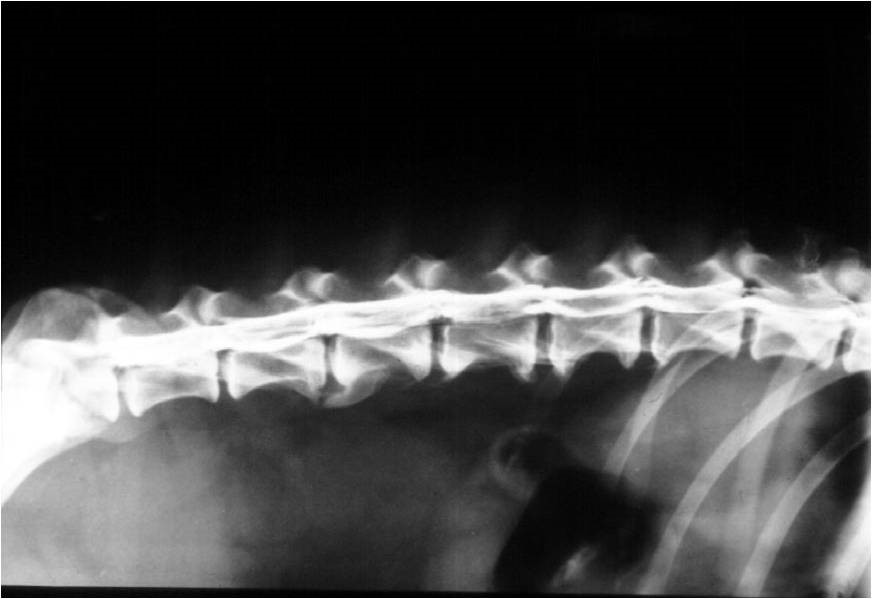

A nyak és a háti gerinc szakasz átmenete